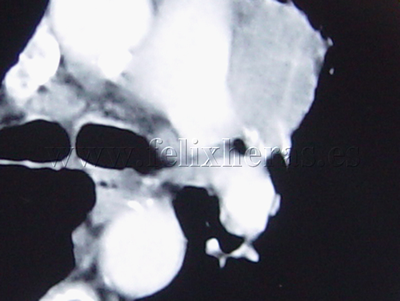

Cáncer de pulmón